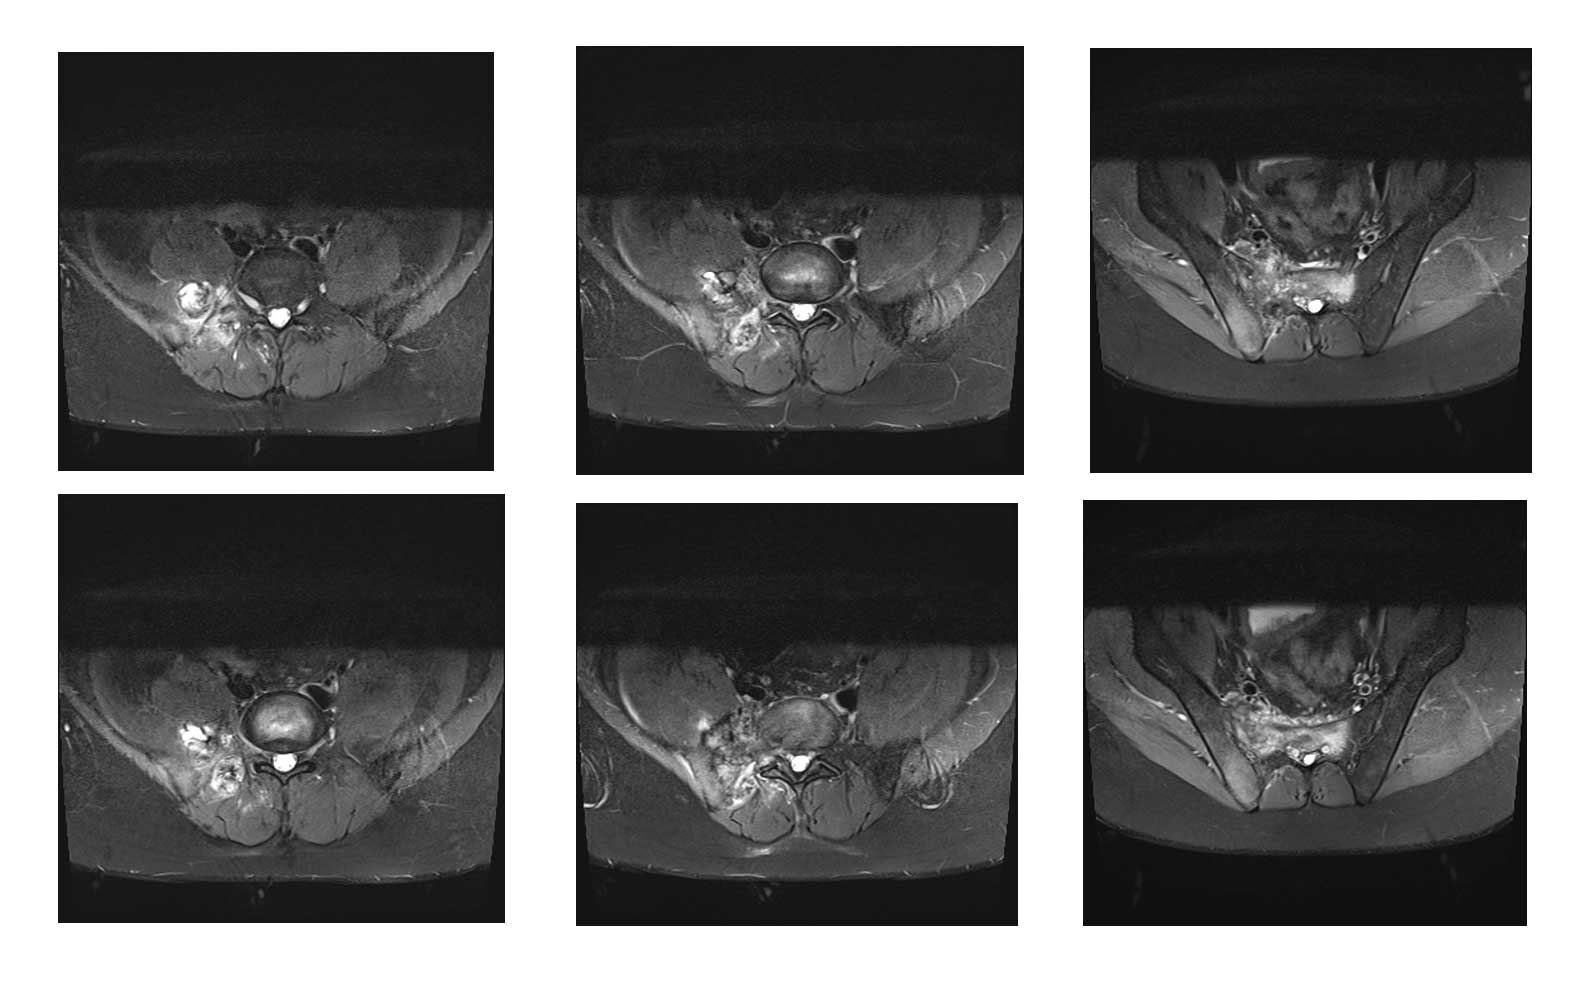

Ameliyat öncesi: MR’da sağ iliak kanat posterior sakroiliak bölge üst kısım ve sakrumun tamamına yakınını kapsayan tümör dokusu ve çevreleyen ödem görülmekte.